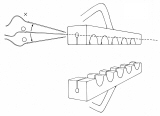

器械吻合器テクニックあれこれ

あのころ、実用化されたばかりの自動吻合器の使用上の「コツ」シリーズ。